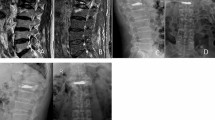

After fracture, vertebroplasty was done using Jamshidi needles (11G) introduced bipedicularly taking special care not to injure the pedicle wall. High-viscosity bone cement polymethylmethacrylate (PMMA, Confidence Spinal Cement System®, DePuy Spine, Raynham, MA, USA) was used to provide better control of cement expansion. Bone cement was injected in increments of 5 % of predetermined fractured vertebral volume to a final injected volume of 20 % of fractured vertebral body volume. The fractured vertebrae were filled in the following way: first bone cement of 5 % of fractured vertebral body volume was injected through one pedicle and the second 5 % (combined 10 %) via the other pedicle. The manoeuvre was repeated for the third (combined 15 %) and fourth (combined 20 % of fractured vertebral volume) injections. Placement of needles and injection of bone cement was monitored closely using alternatively sagittal, frontal and axial plane radiography to show that the needle tips were in the anterolateral part (for the first and second injections) and posterolateral part of the vertebral body (third and fourth injections) as far as possible from lateral borders of vertebrae and vertebral endplates (Fig. 1). Leakage was quantified by collecting the fragments of cement that had leaked and measuring their volume by immersing them in a preset volume of water.

In 6/13 FSU CT images showed vertebral fracture in the upper endplate of the lower vertebra and in the other 7/13 FSU in the lower endplate of the upper vertebra. The average force to produce a vertebral fracture was 4.2 ± 2.5 kN. The height loss was 0.77 ± 0.37 mm.

Cement leakage was detected in 5/52 injections (three times during the first injection, once in the third and once in the fourth injection) in three vertebrae on an average of 0.07 ± 0.03 ml per fill. X-ray images showed cement placement adjacent to the vertebral endplate in 10/52 injections (four after the first and two after the second, third and fourth injections). There was no significant difference in compressive stiffness P = 0.96 and IDP P = 0.23 between the group with cement placement adjacent to endplates compared to the group where cement was nonadjacent to the vertebral endplate.